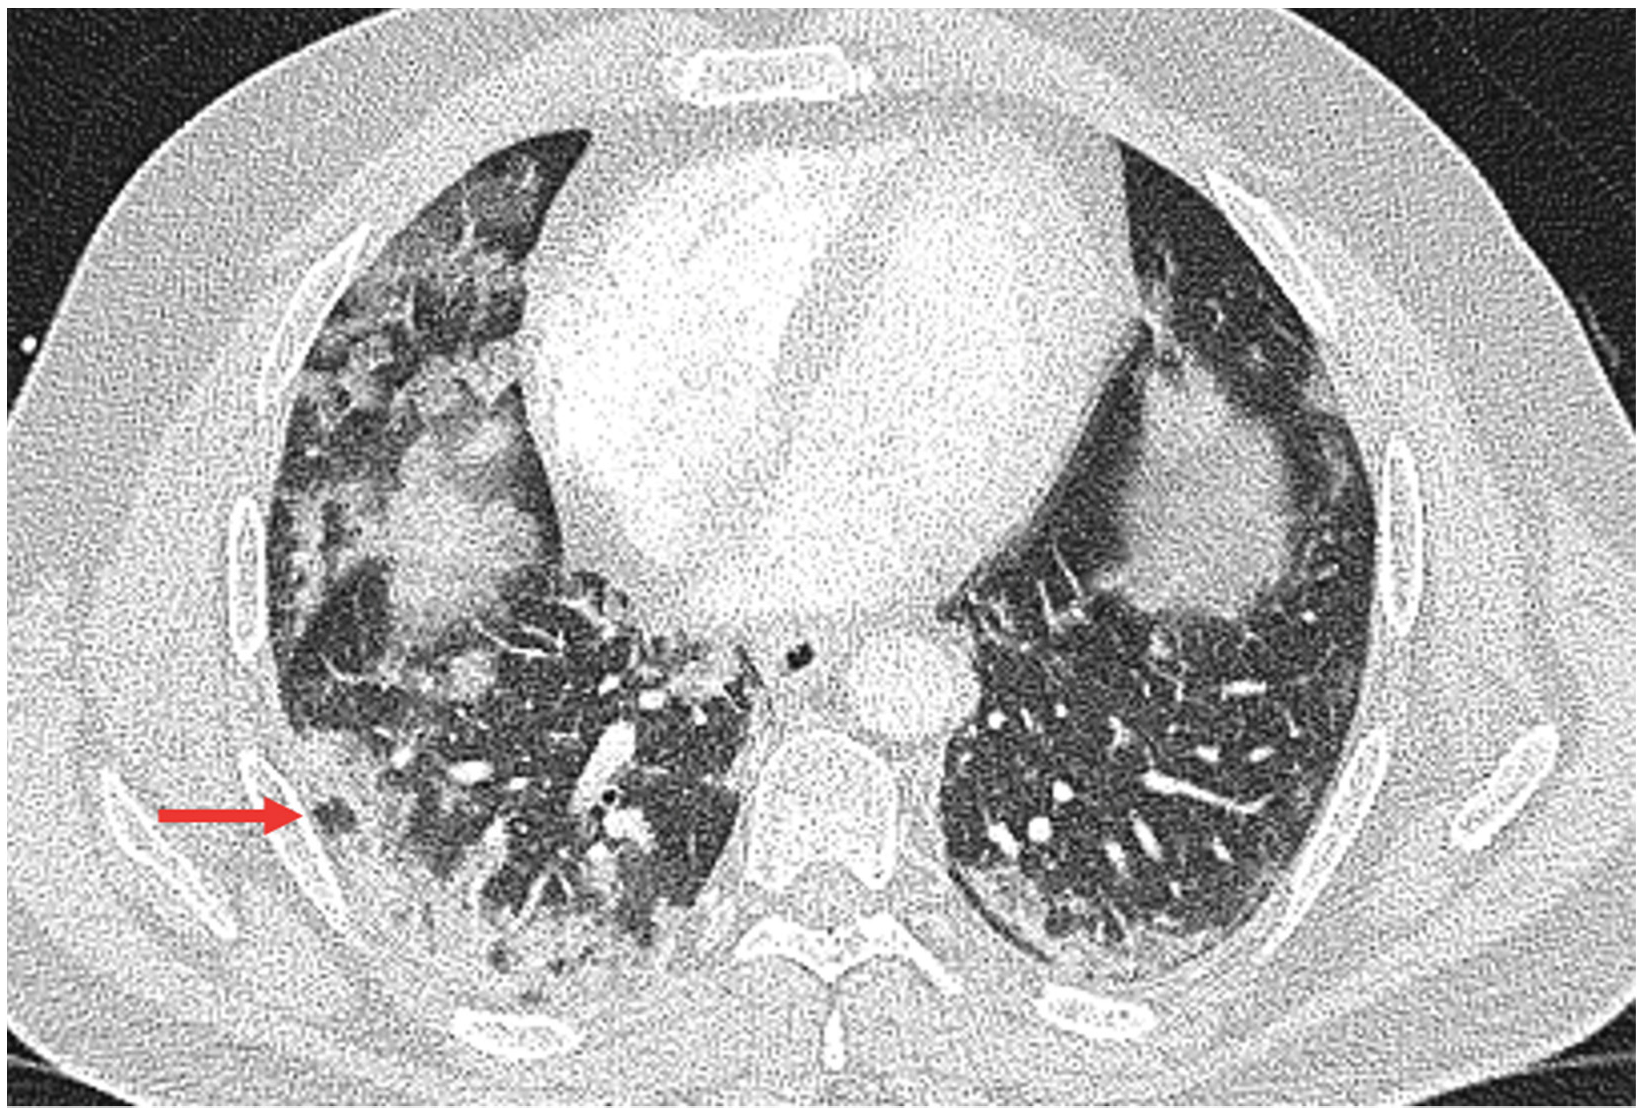

3.2. Qualitative Scoring, Pattern Distribution, Morphology, and Virus Variant

| lung involvement | 0.041 | |||

| no lung involvement single lobe unilateral multilobar bilateral | 11 (18.33%) 1 (1.67%) 2 (3.33%) 46 (76.67%) | 5 (11.63%) 0 (0%) 2 (4.65%) 36 (83.72%) | 6 (35.29%) 1 (5.88%) 0 (0%) 10 (58.82%) | 0.059 0.283 1 0.087 |

| axial distribution | 0.053 | |||

| no predominant distribution peripheral distribution central distribution diffuse distribution | 11 (18.33%) 27 (45.00%) 4 (6.66%) 18 (30.00%) | 5 (11.63%) 23 (53.49%) 2 (4.65%) 13 (30.23%) | 6 (35.29%) 4 (23.53%) 2 (11.76%) 5 (29.41%) | 0.059 0.046 0.317 1 |

| craniocaudal distribution | 0.080 | |||

| no predominant distribution upper lobe predominant lower lobe predominant diffuse | 10 (16.67%) 4 (6.67%) 18 (30.00%) 28 (46.67%) | 4 (9.30%) 4 (9.30%) 13 (30.23%) 22 (51.16%) | 6 (35.29%) 0 (0%) 5 (29.41%) 6 (35.29%) | 0.024 0.570 1 0.390 |

| Pattern Morphology | ||||

| GGO morphology GGO absent subpleural rounded nonrounded, nonperipheral | 15 (25.00%) 28 (46.67%) 2 (3.33%) 15 (25.00%) | 8 (18.60%) 25 (58.14%) 2 (4.65%) 8 (18.60%) | 7 (41.18%) 3 (17.65%) 0 (0%) 7 (41.18%) | 0.014 0.099 0.009 1 0.099 |

| GGO/consolidation | 0.049 | |||

| GGO/consolidation absent predominant extensive predominant nodular GGO/consolidation mixed | 10 (16.67%) 38 (63.33%) 8 (13.33%) 4 (6.67%) | 4 (9.30%) 30 (69.77%) 5 (11.63%) 4 (9.30%) | 6 (35.29%) 8 (47.06%) 3 (17.65%) 0 (0%) | 0.024 0.139 0.676 0.570 |

| Other Pulmonary Findings | ||||

| crazy paving reticulation bronchiectasis bronchial wall thickening tree-in-bud bronchoaerogram vacuolar sign reverse halo sign COP pattern | 15 (25%) 15 (25%) 10 (16.67%) 16 (26.67%) 5 (8.34%) 14 (23.34%) 24 (40.00%) 4 (6.67%) 13 (21.66%) | 14 (32.56%) 10 (23.26%) 6 (13.95%) 9 (20.93%) 4 (9.3%) 13 (30.23%) 23 (53.49%) 4 (9.3%) 11 (25.58%) | 1 (5.88%) 5 (29.41%) 4 (23.53%) 7 (41.18%) 1 (5.88%) 1 (5.88%) 1 (5.88%) 0 (0%) 2 (11.76%) | 0.046 0.743 0.448 0.193 1 0.050 0.001 0.570 0.314 |